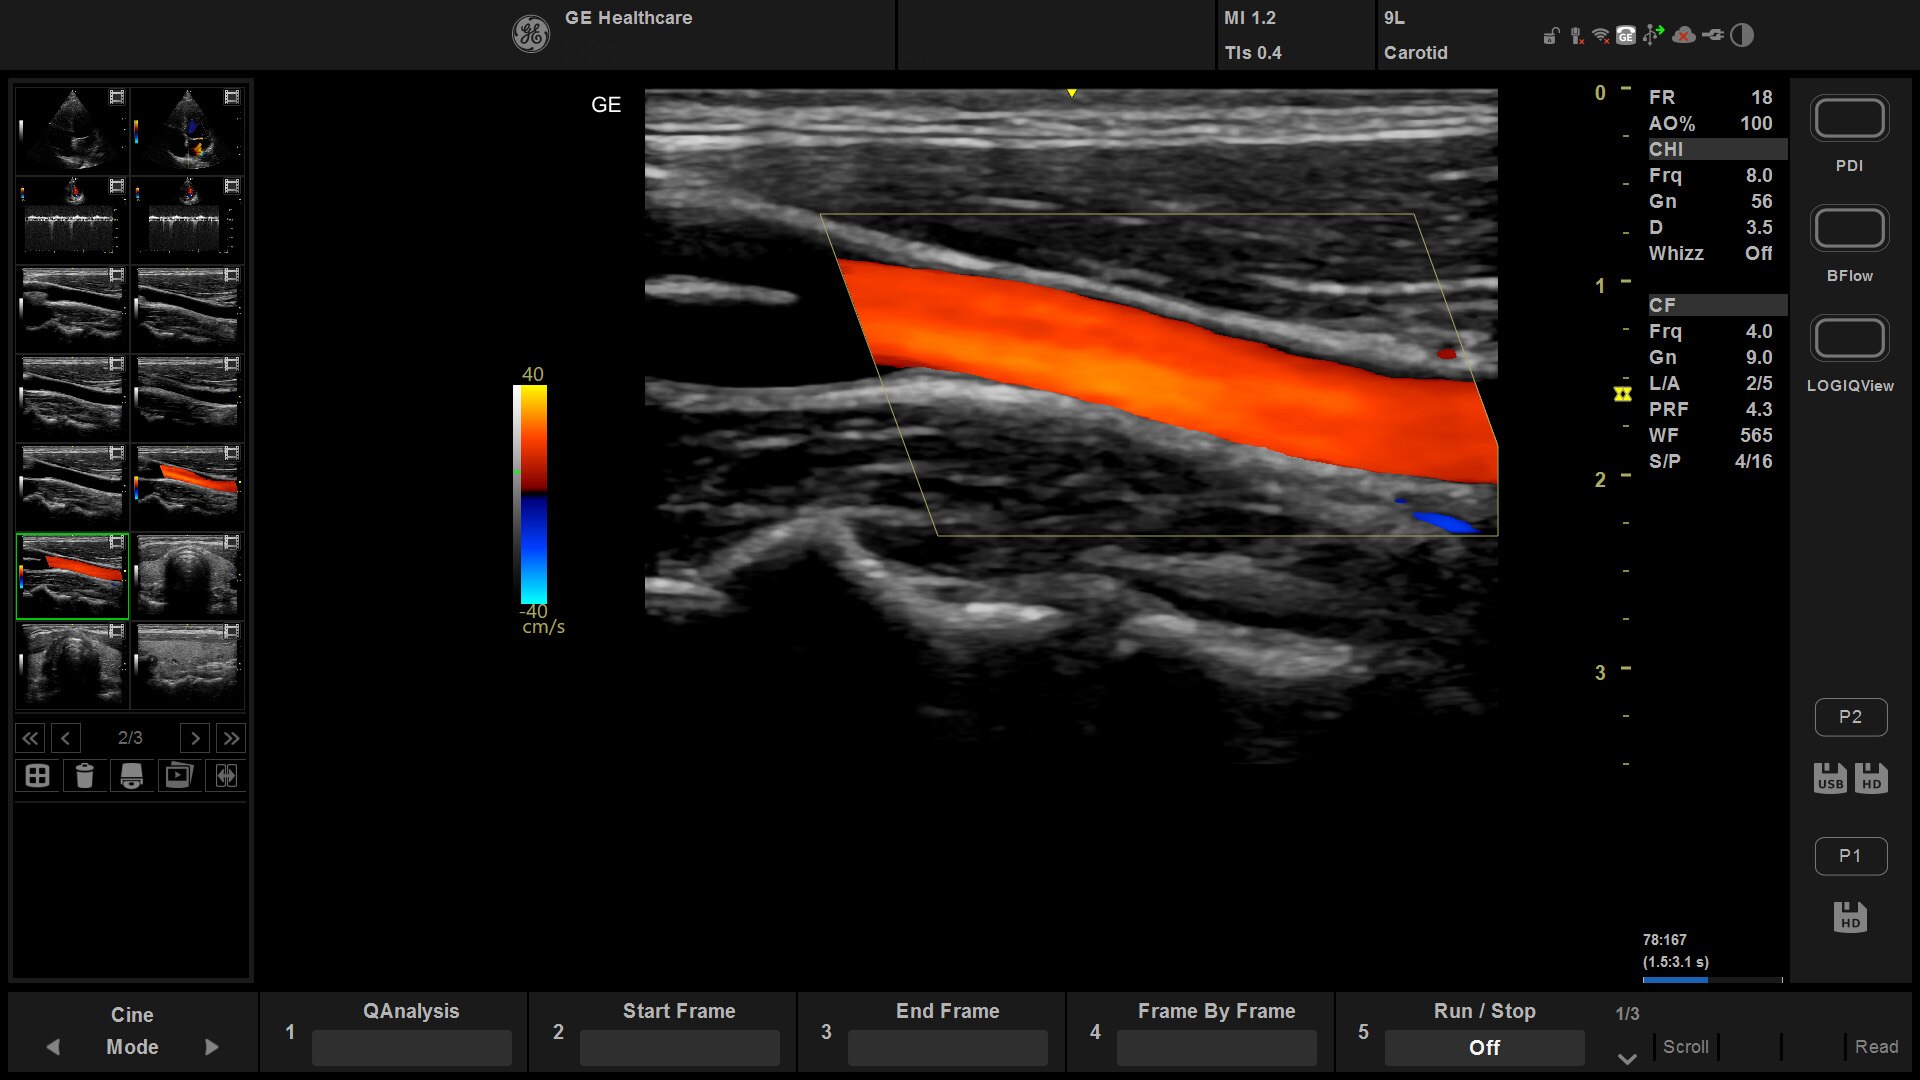

Suited for abdominal, small parts, cardiac, OB/GYN, vascular, and MSK exams

Versana Active delivers the imaging capability of a console in a hand-carried, lightweight package that enables you to actively take your system to your patients, on premises, or remote facilities. The reliable system brings the agility of a laptop unit with the capability for attaching to a cart. Adaptable to cover a broad range of everyday exams, it is easy to carry to clinics, offices, and beyond.

Versana Active features a wide range of advanced clinical applications and automated tools that simplify exams, streamline workflow, and enable fast, high-volume scanning to help you diagnose a wide spectrum of patient conditions.